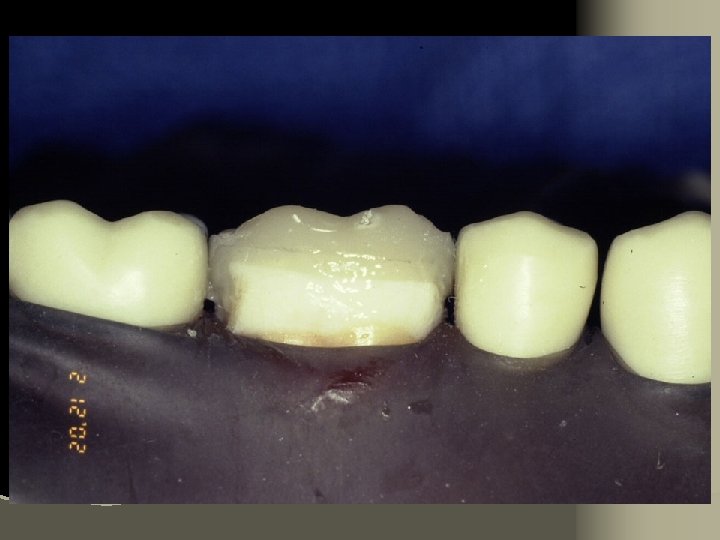

Cementation Procedure 1. Remove temporary and all residue of temporary cement 2. Check occlusion on adjacent teeth (mylar shimstock and articulating paper) 3. Place rubber dam 4. Clean tooth with pumice and rubber cup, rinse and lightly dry 5. Try in restoration for fit.

6. Adjust proximal contacts if necessary 7. Evaluate shade intraorally using water soluble try-in paste (optional) 8. Rinse out try-in paste and air dry 9. Etch inside of restoration (HF porcelain etchant X 2 minutes), rinse with distilled water and air dry 10. Place drop of silane (porcelain primer) on intaglio surface for 1 minute, lightly air thin to evaporate solvent